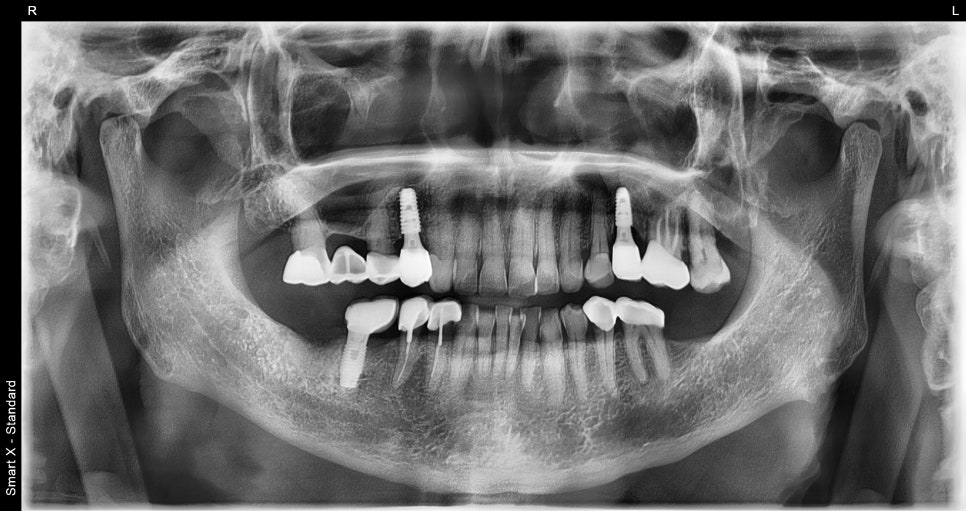

④ Prosthesis placement and completion

– After confirming osseointegration, we connected the abutments → placed the final prosthesis → adjusted the occlusion to finish.

✔️ Being able to chew evenly with both molars improved meal efficiency.

✔️ Temporomandibular joint pain was also greatly relieved, significantly improving overall quality of life.